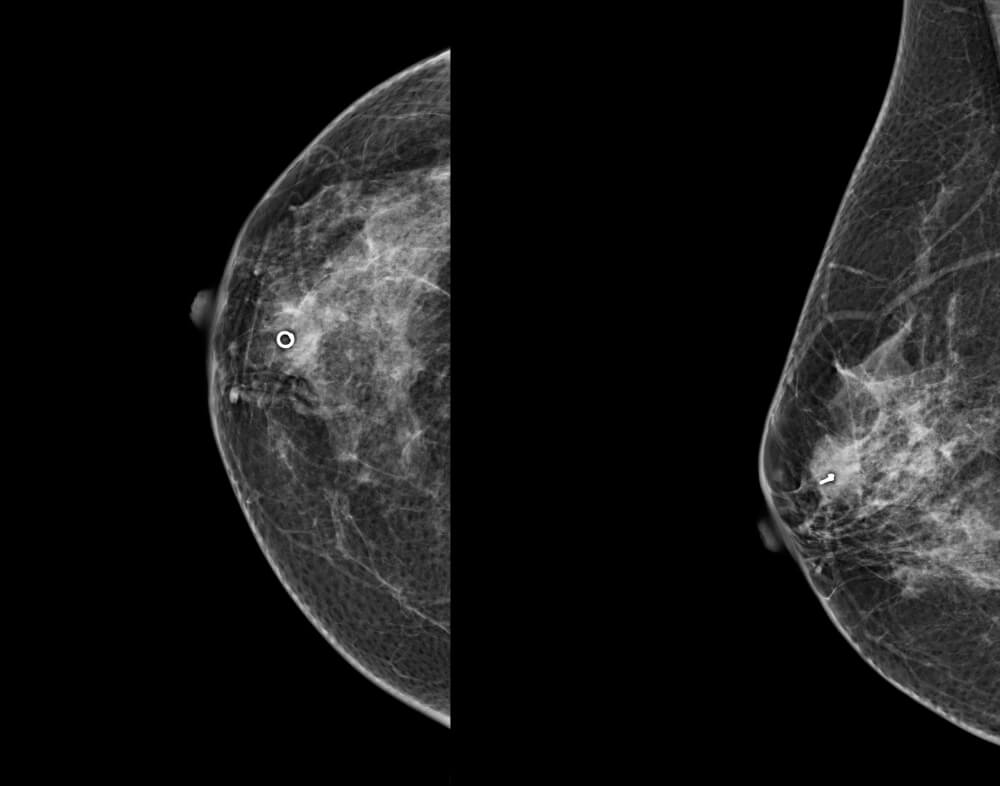

Απαραίτητη προϋπόθεση στις περιπτώσεις αυτές είναι η σήμανση του όγκου με ειδικό σημαντήρα, ώστε, αν μετά την εισαγωγική θεραπεία αυτός εξαφανισθεί, να είναι δυνατός ο εντοπισμός της αρχικής του θέσης για την τελική χειρουργική αντιμετώπιση. Επίσης, σε περίπτωση διασποράς του όγκου σε λεμφαδένες της μασχάλης, είναι απαραίτητη η σήμανση παθολογικών λεμφαδένων με διάφορες τεχνικές.

Στο ιατρείο μας οι όγκοι πριν από την εισαγωγική θεραπεία σημαίνονται με ειδικό σημαντήρα από τιτάνιο με υπερηχογραφική καθοδήγηση.

Μετά την τοποθέτηση του σημαντήρα καταγράφεται η σχέση του προς τον όγκο και επιπλέον η θέση του επιβεβαιώνεται, τις περισσότερες φορές, με μαστογραφία.

Κατά την τελική χειρουργική αντιμετώπιση, η θέση του σημαντήρα εντοπίζεται με την τοποθέτηση ειδικού συρμάτινου οδηγού (hook wire) είτε προεγχειρητικά με την βοήθεια μαστογράφου ή συσκευής υπερήχων είτε κατά την διάρκεια του χειρουργείου με την χρήση υπερήχων.